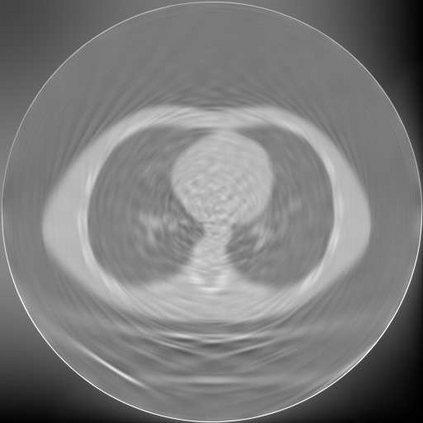

Sparse-view computed tomography (CT) is known as a widely used approach to reduce radiation dose while accelerating imaging through lowered projection views and correlated calculations. However, its severe imaging noise and streaking artifacts turn out to be a major issue in the low dose protocol. In this paper, we propose a dual-domain deep learning-based method that breaks through the limitations of currently prevailing algorithms that merely process single image slices. Since the scanned object usually contains a high degree of spatial continuity, the obtained consecutive imaging slices embody rich information that is largely unexplored. Therefore, we establish a cascade model named LS-AAE which aims to tackle the above problem. In addition, in order to adapt to the social trend of lightweight medical care, our model adopts the inverted residual with linear bottleneck in the module design to make it mobile and lightweight (reduce model parameters to one-eighth of its original) without sacrificing its performance. In our experiments, sparse sampling is conducted at intervals of 4{\deg}, 8{\deg} and 16{\deg}, which appears to be a challenging sparsity that few scholars have attempted before. Nevertheless, our method still exhibits its robustness and achieves the state-of-the-art performance by reaching the PSNR of 40.305 and the SSIM of 0.948, while ensuring high model mobility. Particularly, it still exceeds other current methods when the sampling rate is one-fourth of them, thereby demonstrating its remarkable superiority.